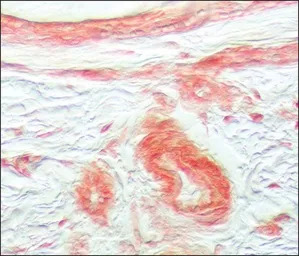

IHC-P analysis of human umbilical cord sections using GTX10646 FGFR1 antibody at 5 μg/mL.

IHC-P analysis of human umbilical cord section using GTX10646 FGFR1 antibody at 5 μg/mL.